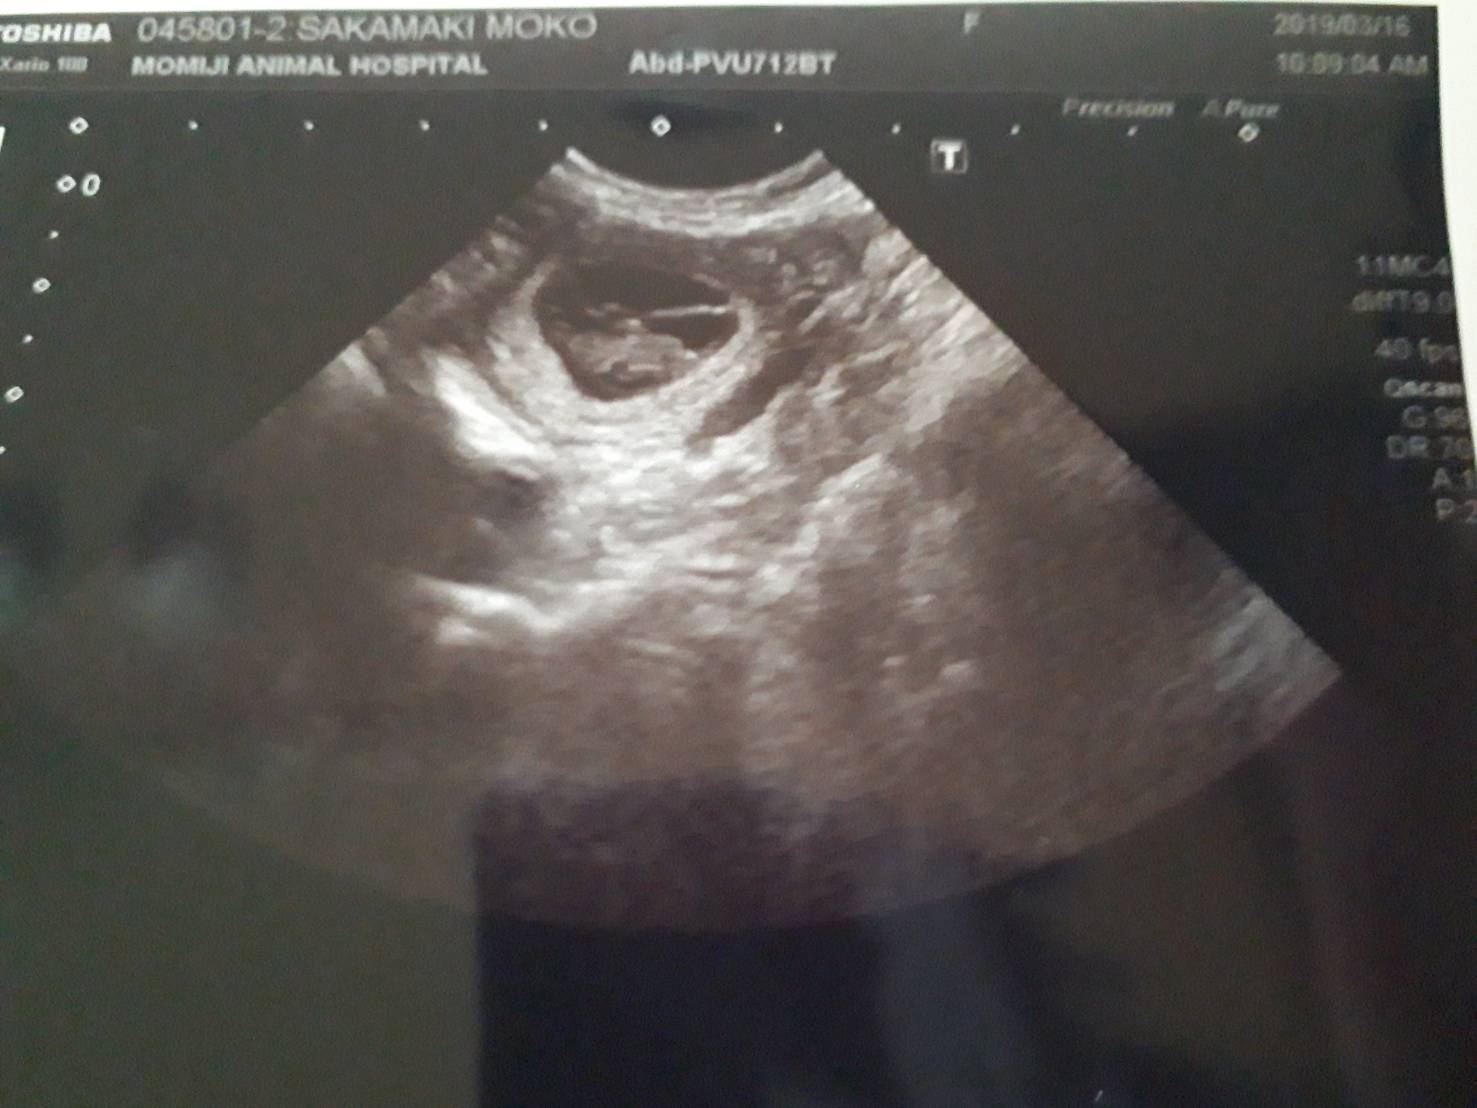

H31.3.16 ④

超音波検査の結果、3頭以上を確認できました♪

H31.3.16 ③

超音波検査の様子です♪

お利口に仰向けになってます(^_^)

H31.3.16 ②

妊娠検診中

もこちゃん、少し緊張ぎみ(^_^;)

H31.3.16 ①

もこちゃん、妊娠検診のため、もみじ動物病院で診察待ち